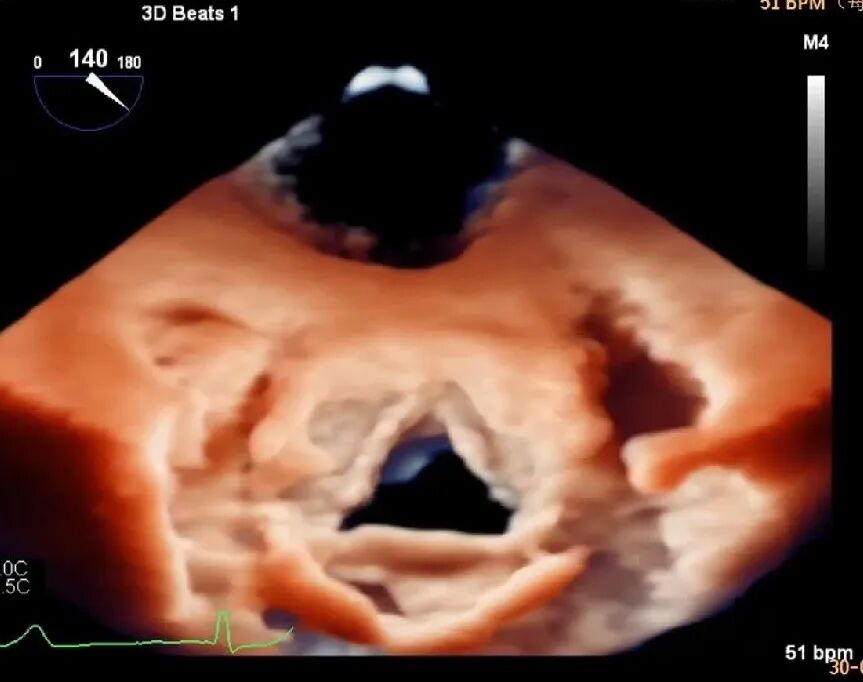

为了精准找到病因,超声医学科主任郑瑜团队立即为患者安排了终极武器——四维全景经食道超声心动图,由赵洁副主任医师为患者进行检查,检查结果震撼呈现。通过非常炫酷和逼真的动态4D立体成像技术,清晰捕捉到主动脉瓣瓣叶上附着1个形态不规则的团块状回声——这就是感染性心内膜炎的“元凶”瓣膜赘生物!很小但很清晰,它像悬在心脏里的小炸弹,随时可能脱落引发动脉栓塞,但还算万幸,患者瓣膜的活动度和关闭尚未受到明显影响,为后续治疗提供了可靠依据。

3D立体还原:实时构建心脏三维动态模型,把瓣膜结构、病灶形态以立体视角完整呈现,微小病灶也能精准捕捉;